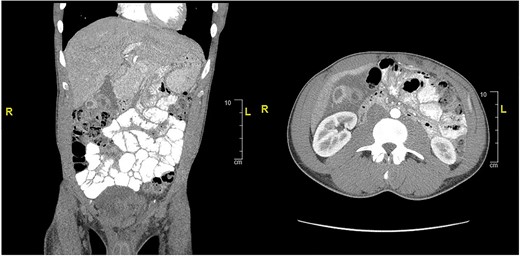

CT of abdomen and pelvis showing an inflamed gallbladder with fistulous communication within the hepatic flexure of the colon. Large descending colon enterolith (4.5 × 4.3 × 8.0 cm). Apparent pneumobilia.

Case presentation # 1: An 80-year-old female with congestive heart failure and hypertension, presented to the emergency room with 4 days of diffuse abdominal pain associated with nausea, vomiting and anorexia. She was hemodynamically stable upon presentation, with upper abdominal tenderness on exam. Initial imaging (Figs 1 and 2) was obtained, showing a CCF with large bowel obstruction caused by an 8-cm gallstone in the descending colon. The patient was taken to the operating room for an exploratory laparotomy, where upon inspection a large gallstone in the descending colon and a fistulous communication between the gallbladder and hepatic flexure of the colon were noted. Takedown of the fistula was attempted, however because of extensive colonic involvement a decision was made to perform a right hemicolectomy with primary anastomosis, as well as a partial cholecystectomy at the level of infundibulum due to chronic inflammation and thickening of the gallbladder. The gallstone was taken out with the specimen (Fig. 3). The postoperative course was significant for exacerbation of heart failure, but ultimately, she was discharged home upon successful tolerance of a regular diet with return of bowel function.